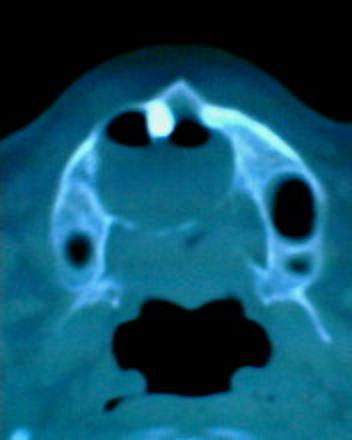

患者:男71岁,右侧上颚肿物无痛性生长7年.

右上颌骨近中线部见类圆形低密度区,上方见一液平,周围见一薄硬化环,前下方见一牙根,后方累及水平板。上方突入鼻腔前下部,下方突入口腔。

考虑:右侧上颌骨囊肿伴感染。